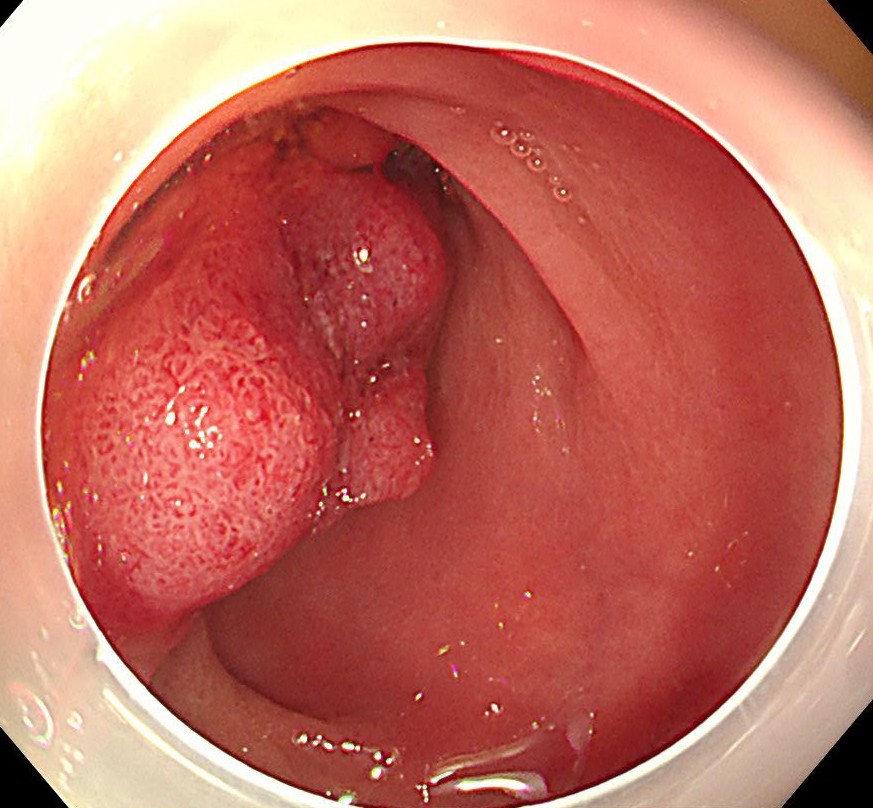

直腸S状結腸移行部に1型の腫瘍を認めます。